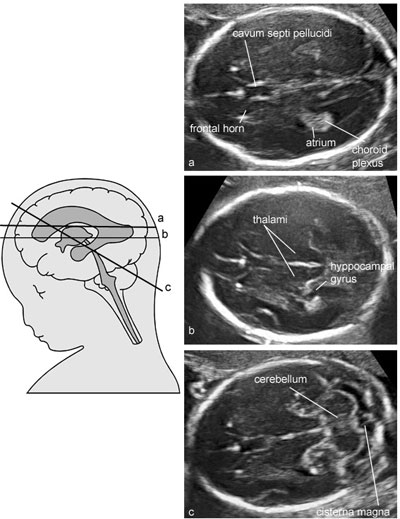

26.28歲孕婦,G2P1,妊娠16週,接受超音波檢查如圖所示,下列何者為最可能的診斷?

(A)anencephaly

(B)holoprosencephaly

(C)choroid plexus cyst

(D)Dandy-Walker malformation